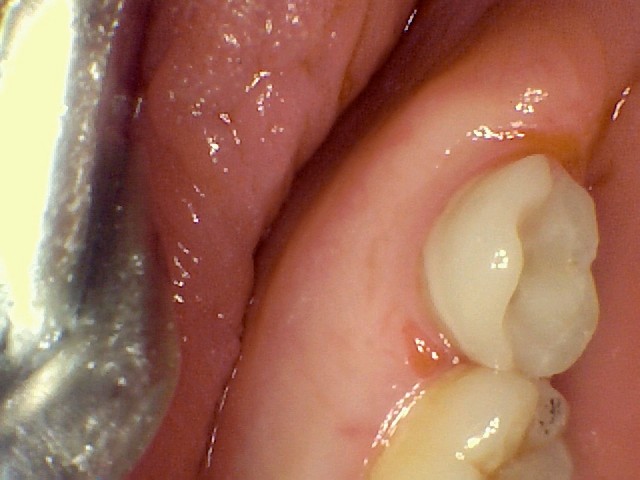

Cavity, prep and restoration